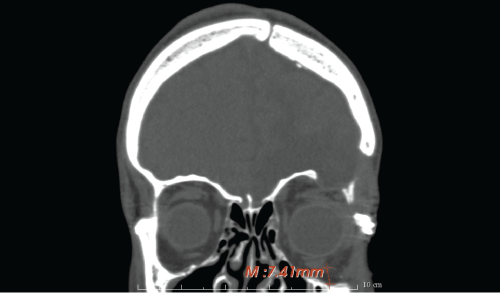

The patient's anatomy was then assessed in multiplanar (axial, coronal, sagittal) and 3D computed tomography via Toshiba Aquilon One Helical CT scanner (Figure 2), gantry = 0, slice = 1mm. The orbital floor malposition on the left side was, as measured through the CT images, 7.4 mm caudal than the contralateral one (Figure 3), causing ocular dystopia. DICOM files were processed by DeVIDE software to a .stl file. Then Netfabb software was used to obtain an ABS polymeric stereolithographic model via HP Designjet 3D printer (Figure 4). A silicon impression material was manually adapted on the stereolithopraphic model defective orbital floor to achieve a steam sterilizable autoclavable mould as a helping device in manual bone graft modelling during the surgery.